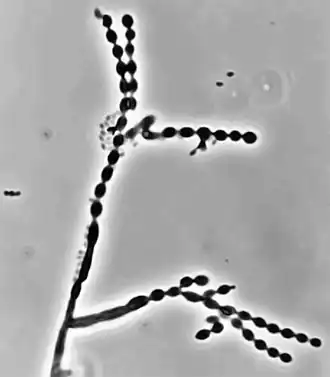

Individuen der Gattung haben ein schwärzliches, mikroskopisch an Hefen erinnerndes Aussehen. Sie bilden verzweigte Ketten mit ovalen bis fusiformen (spindelartigen) Konidien (Sporen). Sie wachsen moderat bis langsam und bilden aufgrund von Melaninbildung dunkle Kolonien von unterschiedlicher Farbe (dunkelgrün, dunkelgrau, schwarz) mit samtiger Oberfläche in einer Größenordnung bis etwa 3 cm, mit gut definiertem, dunklen Randsaum.[2][3] Die Conidiophoren (sporentragende Strukturen) präsentieren sich mikroskopisch lang und verzweigt.[4] Die Conidien selbst können unterschiedlich aussehen, z. B. glatt oder rau und ein- bis mehrzellig sein und bis zu 4 µm Länge erreichen, bei 3 µm Durchmesser.[2]